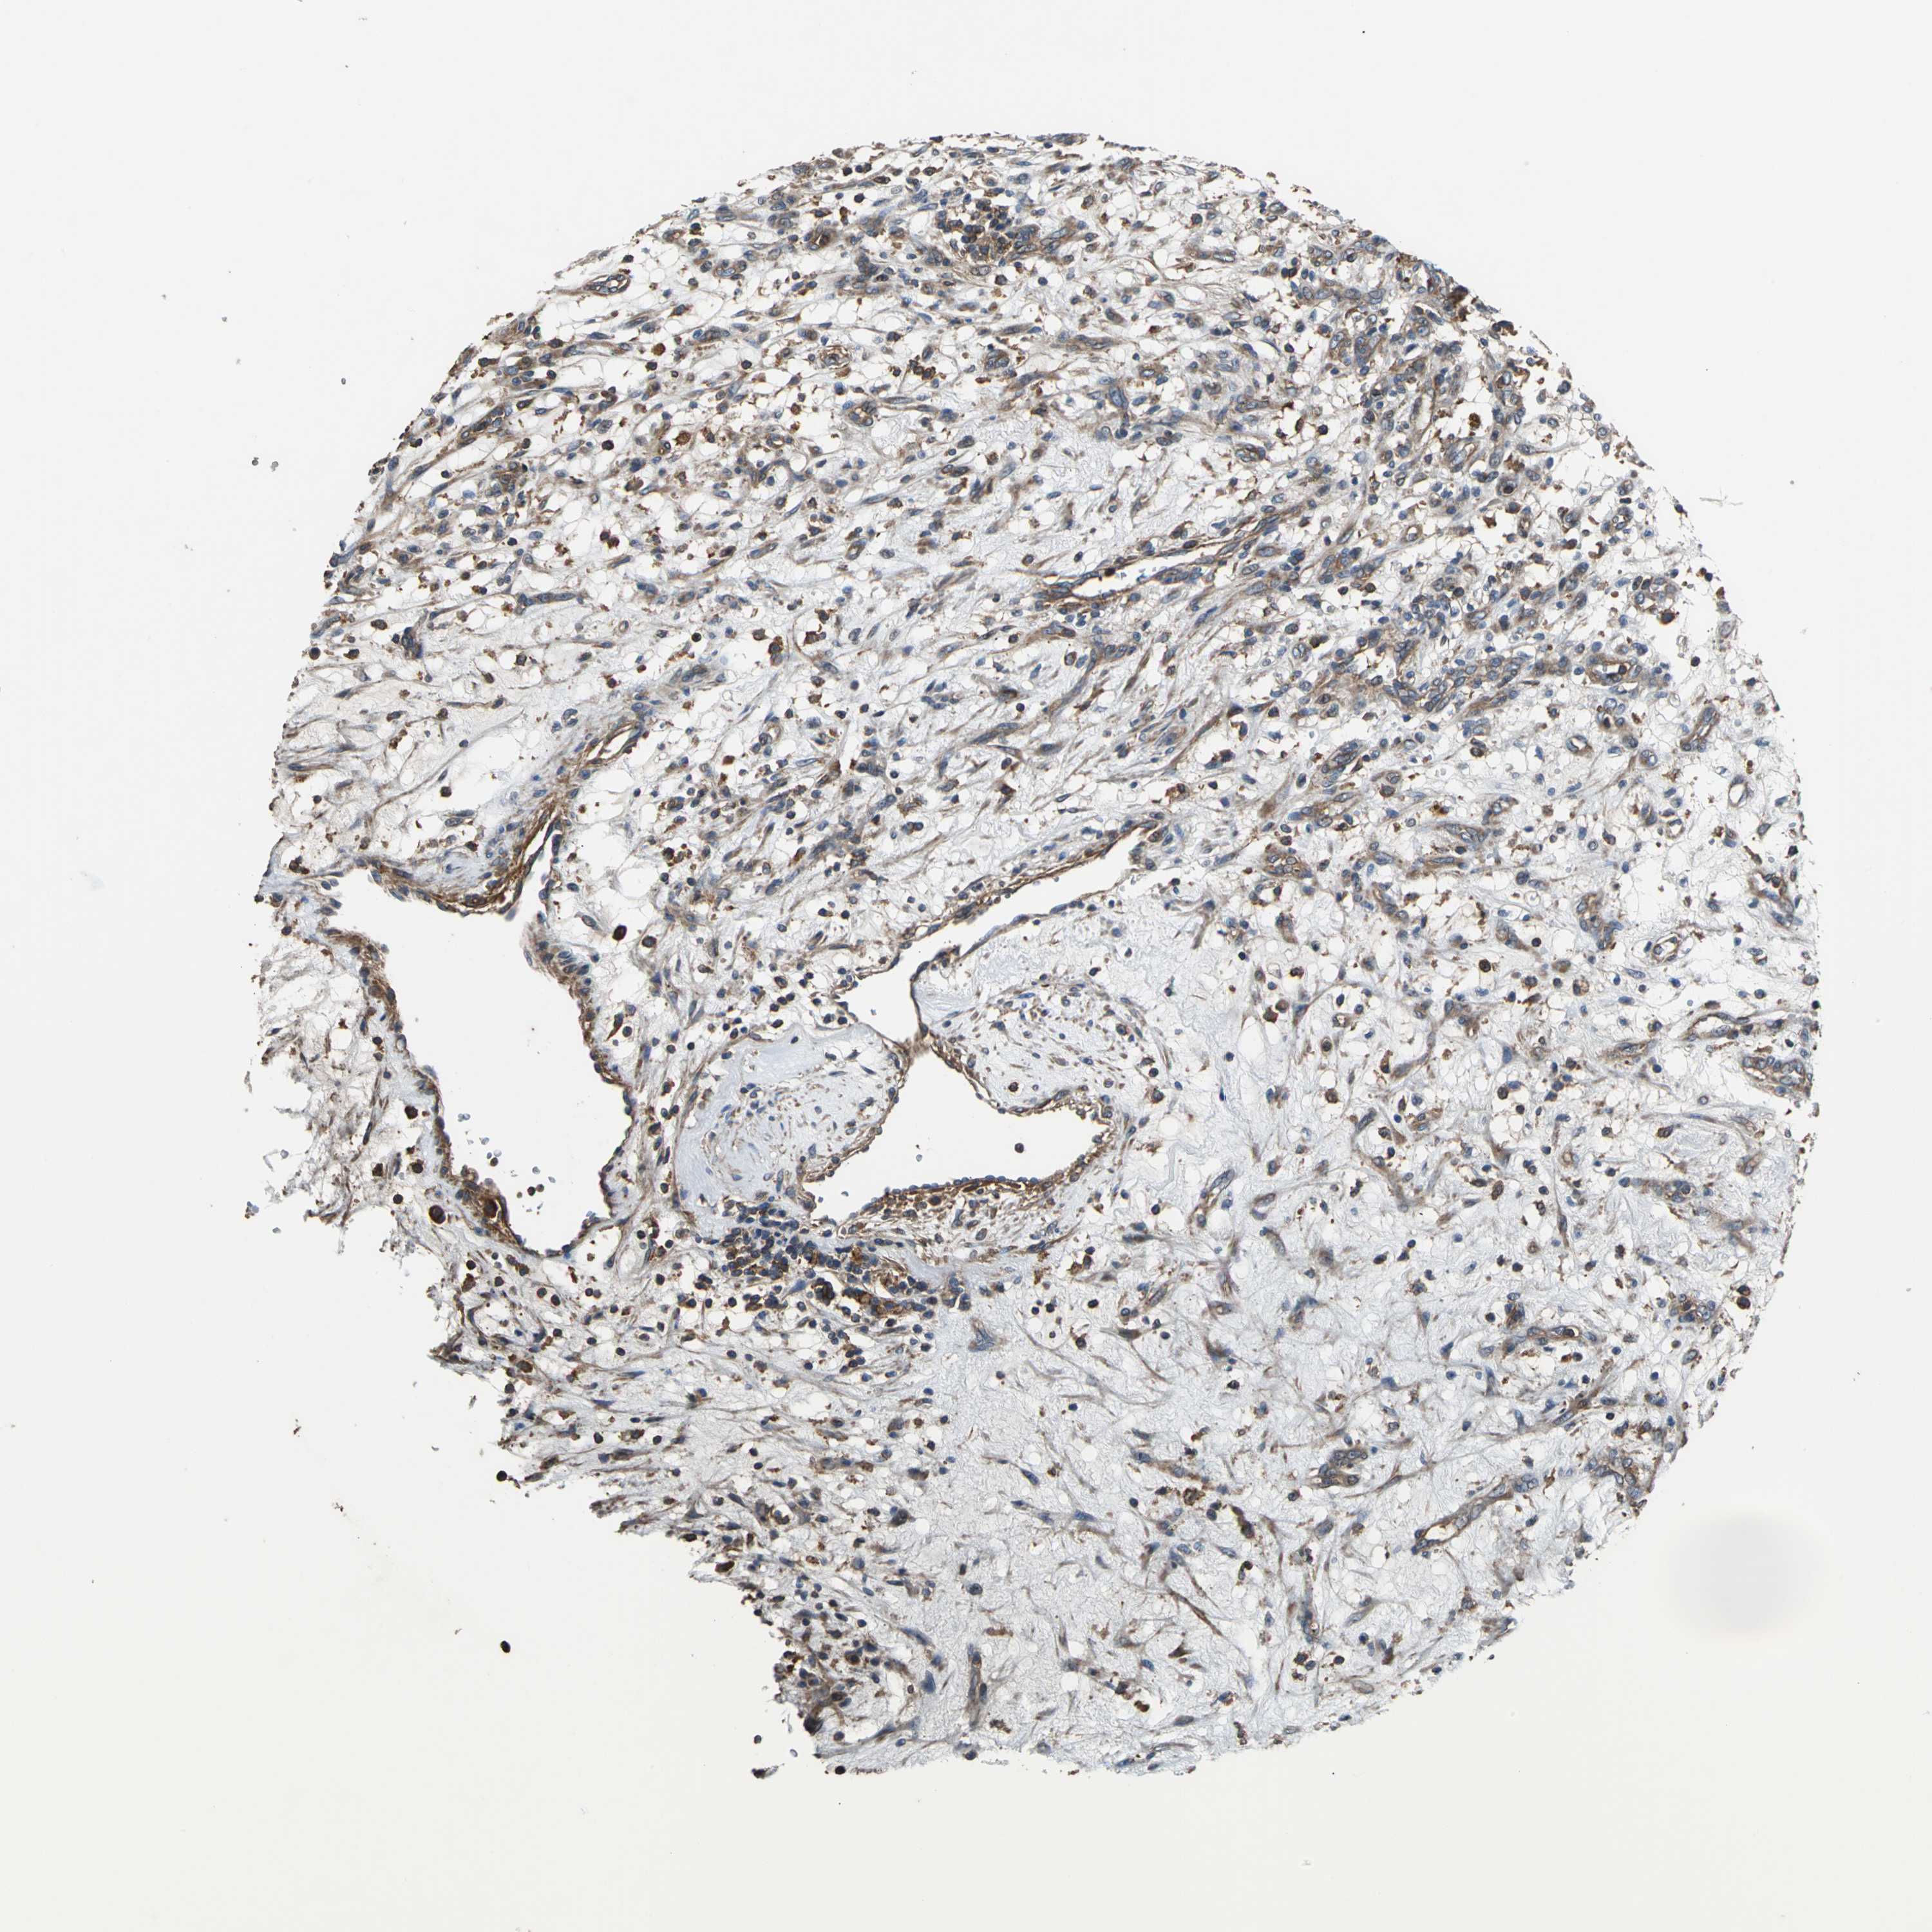

KIDNEY RENAL CLEAR CELL CARCINOMA (VALIDATION) - Interactive survival scatter ploti

The Survival Scatter plot shows the clinical status (i.e. dead or alive) for all individuals in the patient cohort, based on the same data that underlies the corresponding Kaplan-Meier plots. Patients that are alive at last time for follow-up are shown in blue and patients who have died during the study are shown in red.

The x-axis shows the expression levels (FPKM) of the investigated gene in the tumor tissue at the time of diagnosis. The y-axis shows the follow-up time after diagnosis (years). Both axes are complimented with kernel density curves demonstrating the data density over the axes. The top density plot shows the expression levels (FPKM) distribution among dead (red) and alive patients (blue). The right density plot shows the data density of the survived years of dead patients with high and low expression levels respectively, stratified using the cutoff indicated by the vertical dashed line through the Survival Scatter plot. This cutoff is automatically defined based on the FPKM cutoff that minimizes the p-score. The cutoff can be changed by dragging the vertical line or by entering a cutoff value in the square labeled "Current cut-off".

Under the Survival Scatter plot the p-score landscape (black curve; left axis) is shown together with dead median separation (red curve; right axis). Dead median separation is the difference in median mRNA expression between patients who have died with high and low expression, respectively. It is calculated as follows: median FPKM expression of dead patients with high expression - median FPKM expression of dead patients with low expression. This is intended to aid the user in visually exploring custom cutoffs and the associated p-scores and dead median separation.

Individual patient data is displayed and can be filtered by clicking on one or more of the category buttons on the top of the page. Categories describing expression level and patient information include: high, low, alive, dead, female, male and tumor stages. The scale of the x-axis can be toggled between linear and log-scale by clicking on the "x log" button. Mouse-over function shows TCGA ID, patient information and mRNA expression (FPKM) for each patient.

& Survival analysisi

Kaplan-Meier plots summarize results from analysis of correlation between mRNA expression level and patient survival. Patients were divided based on level of expression into one of the two groups "low" (under cut off) or "high" (over cut off). X-axis shows time for survival (years) and y-axis shows the probability of survival, where 1.0 corresponds to 100 percent.

PARVA is not prognostic in Kidney Renal Clear Cell Carcinoma (validation)

Best expression cut offi

Based on the FPKM value of each gene, patients were classified into two groups and association between prognosis (survival) and gene expression (FPKM) was examined. The best expression cut-off refers the FPKM value that yields maximal difference with regard to survival between the two groups at the lowest log-rank P-value. Best expression cut-off was selected based on survival analysis .

When clicking on this number, the vertical dashed line indicating cut-off, the interactive survival plot, and the Kaplan-Meier curve will be adjusted to show results based on the best expression cut-off.

: 37.21

TCGA RNA samplesi

RNA-seq data is reported as average FPKM (number Fragments Per Kilobase of exon per Million reads), generated by the The Cancer Genome Atlas (TCGA) .

Normal distribution across the dataset is visualized with box plots, shown as median and 25th and 75th percentiles. Points are displayed as outliers if they are above or below 1.5 times the interquartile range. FPKM values of the individual samples are presented next to the box plot.

Average pTPM 30.7

Number of samples 100